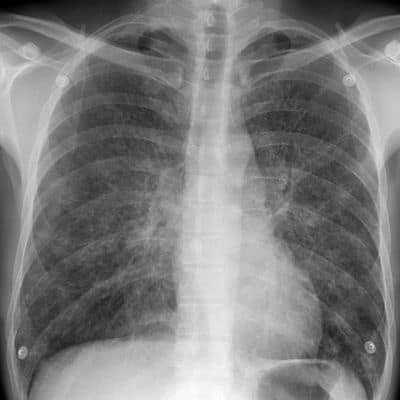

Л. М.: – Естественно, что кашель с отхождением мокрот — это не всегда явный признак туберкулёза. Необходимо провести диагностику заболевания. Для этого используется рентгенологическое сканирование лёгких, микроскопическое исследование отходящих при кашле мокрот и прочие клинические обследования.

Для взрослых основным методом диагностики является флюорография, которая проводится ежегодно в поликлинике по месту жительства.

- рентгенография;

Началом обследования является проведение флюорографии, рентгенографии, позволяющее определить воспалительный процесс в легких. У большинства пациентов заболевание излечимо. Основным правилом успешной терапии является полное соблюдение режима приема препаратов, выполнение других назначений врача.